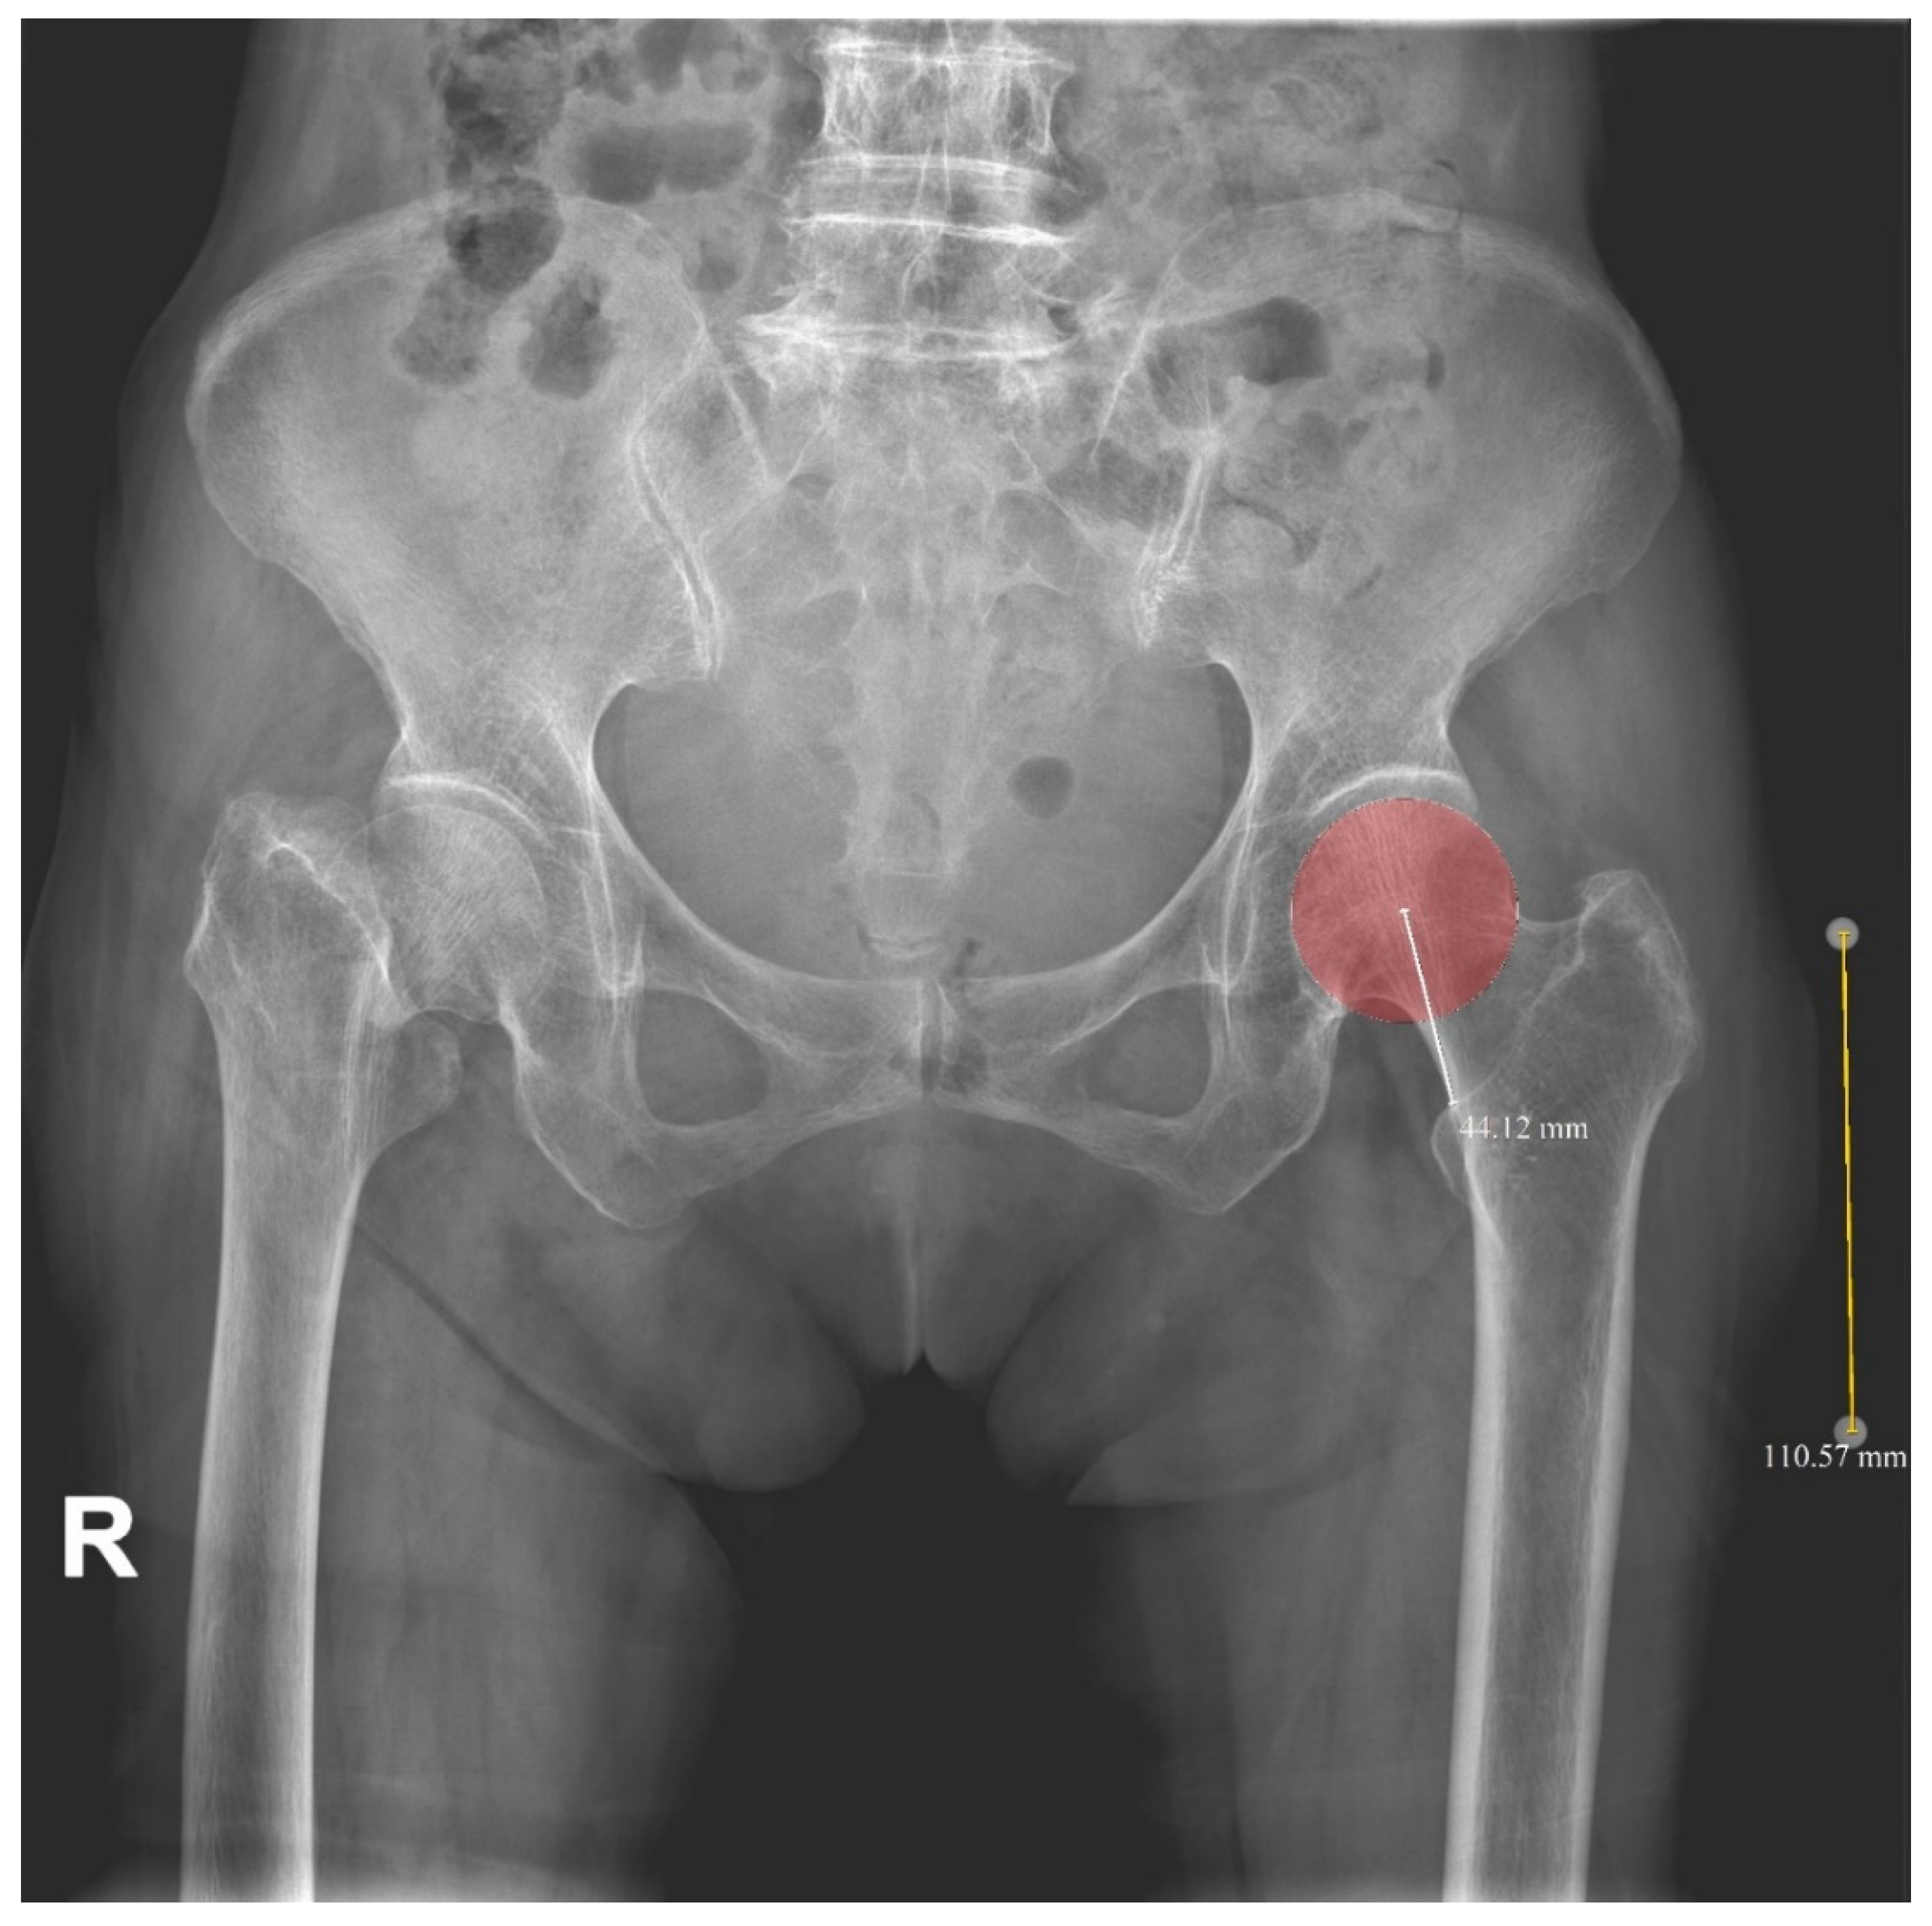

2.2. Radiologic Parameters

| 2-D HLD | 43.4 ± 4.5 | 43.1 ± 3.9 | 0.710 |